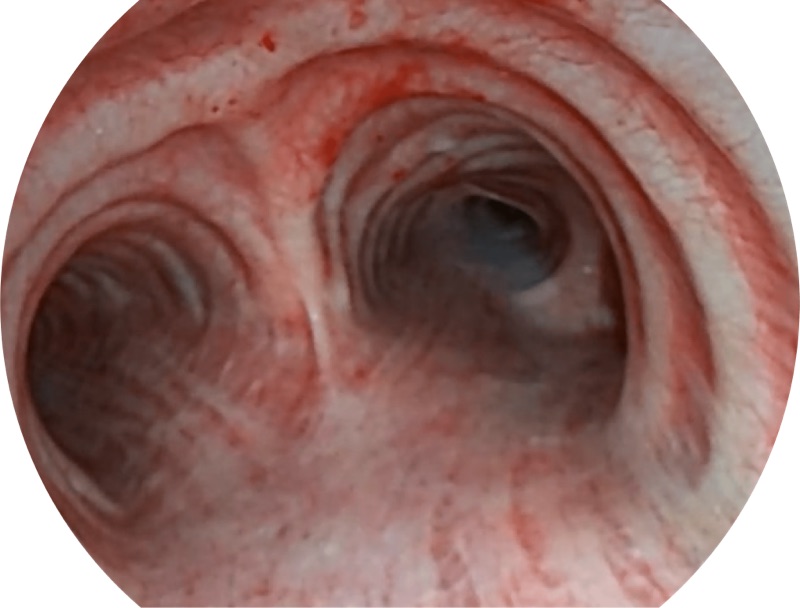

EB-5H20具有4.9mm外径及2.0mm钳道提升对外围支气管检查能力

帮助医生更加清晰地观察气管表面病灶